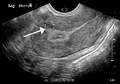

A very large (9 cm) fibroid of the uterus which is causing pelvic congestion syndrome as seen on ultrasound |

While a bimanual examination typically can identify the presence of larger fibroids, gynecologic ultrasonography (ultrasound) has evolved as the standard tool to evaluate the uterus for fibroids. Sonography will depict the fibroids as focal masses with a heterogeneous texture, which usually cause shadowing of the ultrasound beam. The location can be determined and dimensions of the lesion measured. Also magnetic resonance imaging (MRI) can be used to define the depiction of the size and location of the fibroids within the uterus.